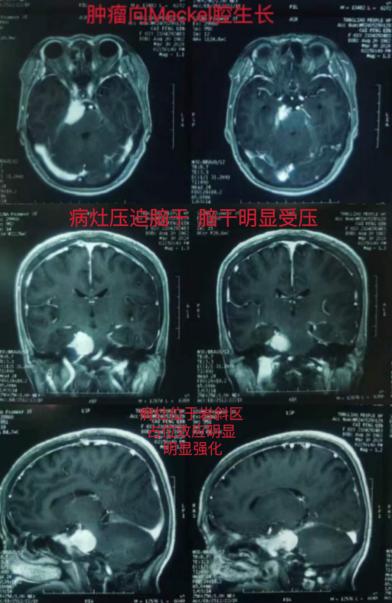

患者,女性,61岁,因发现颅内占位5年,近期面部疼痛难忍,严重影响生活,慕名我院赵林主任特来求诊。经检查诊断为:右侧岩斜区占位,考虑脑膜瘤,因肿瘤长入Meckel腔导致三叉神经受压引起三叉神经痛。岩斜区脑膜瘤临床较少见,因其病变位于中央颅底,周围重要神经血管结构复杂,故手术难度大,风险高,是颅底肿瘤手术中具有代表性疾患之一。与患者及家属充分沟通后,决定接受手术治疗。

经科室讨论后,决定采取右侧Kawase入路,硬膜外磨除岩尖Kawase三角骨质,扩大显露后颅窝空间,便于更好地切除肿瘤及保护重要神经、血管结构。术中肿瘤全切,血管神经均得到良好保留,手术历时10小时顺利完成。术后病理结果为右侧岩斜区脑膜瘤。术后患者恢复良好,生命体征平稳,四肢活动自如,无面神经、三叉神经及后组颅神经功能障碍,术后12天痊愈出院。